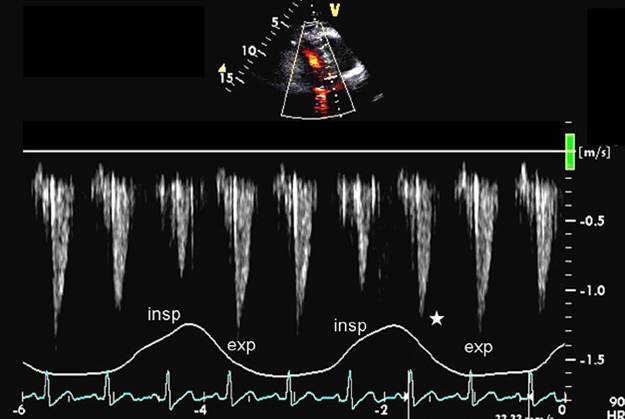

缩窄性心包炎,多普勒血流频谱

组织多普勒e’

缩窄性心包炎